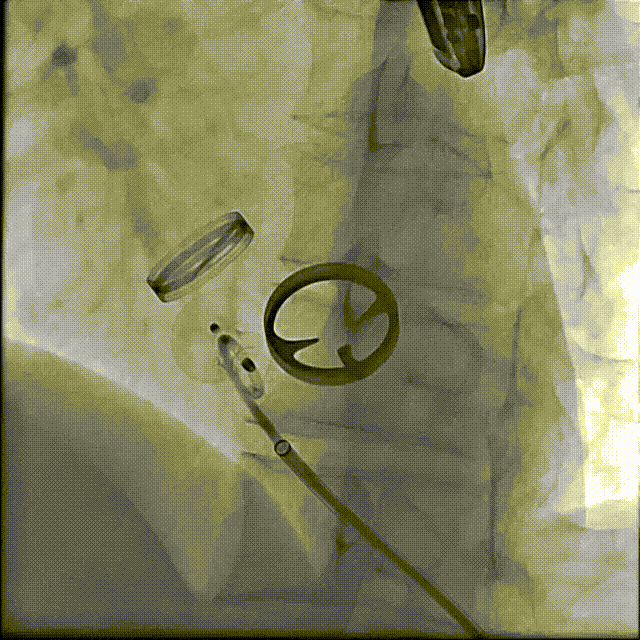

术后封堵器形态位置

1.患者平卧位,食道超声检查瓣周漏位置及大小,并引导穿刺心尖,选择7F鞘管通过10点位置瓣周漏口,将单弯导管送入左心室,置换超硬导丝至左心室,选择12-14mmPDAO封堵10点位漏口。

3.选择7F鞘管通过1-2点位置瓣周漏,彩超显示鞘管对瓣周漏口的影响较小,结合漏口大小,选择14-16mmPDAO封堵此处漏口。